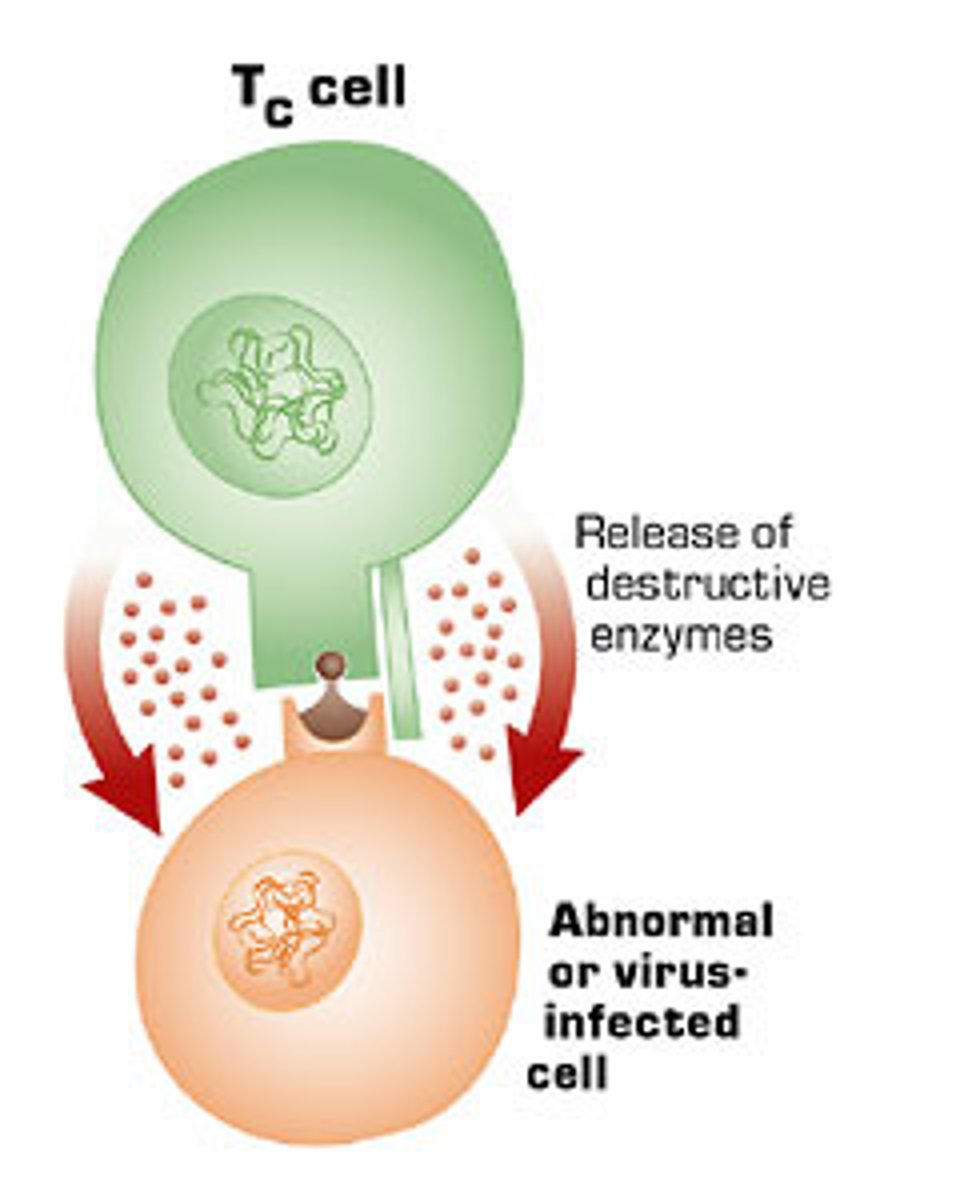

T cells

A type of lymphocyte that is created in the thymus; produce substances that attack infected cells in the body

CD8 T cells

Cytotoxic T cells

A type of effector T-cell; they target and kill invading pathogens and cancer cells